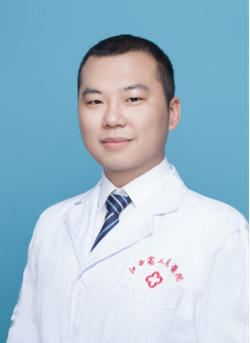

李宇旭 骨科脊柱病区诊疗组组长,副主任医师,博士(在读)

擅长:脊柱畸形、脊柱退变及脊柱创伤疾病的诊治,在颈椎、腰椎疾病的诊治及微创治疗方面有独到的见解,拥有大量的脊柱内镜手术经验,2022年于江西省人民医院首次开展“UBE”脊柱微创技术,并将其广泛应用于颈椎、胸椎、腰椎等脊柱手术,取得了良好的疗效。

门诊时间:周五下午(红谷滩院区)